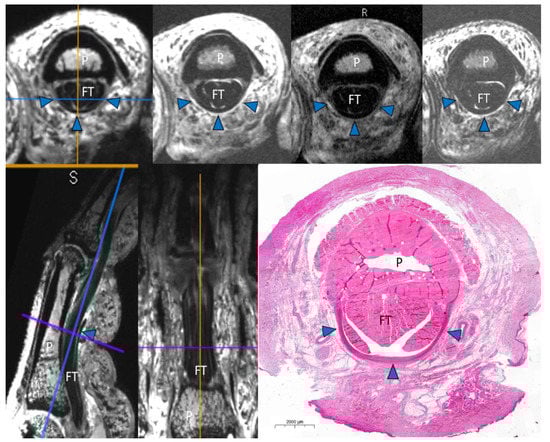

MRI of Finger Pulleys at 7T—Direct Characterization of Pulley Ruptures in an Ex Vivo Model

Heiss, R.; Librimir, A.; Lutter, C.; Janka, R.; Kuerten, S.; Roemer, F.W.; Nagel, A.M.; Uder, M.; Bayer, T. MRI of Finger Pulleys at 7T—Direct Characterization of Pulley Ruptures in an Ex Vivo Model. Diagnostics 2021, 11, 1206. https://doi.org/10.3390/diagnostics11071206